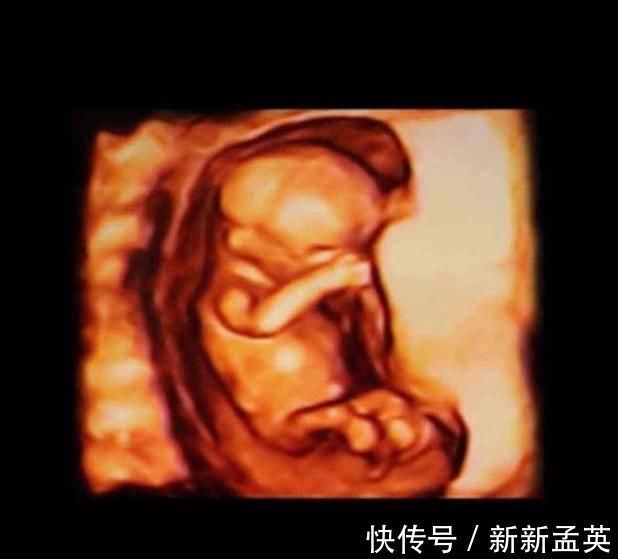

13-15周,胎儿的眼睛开始转动,大脑也在飞速地发育,胎儿的小脸已经和成人差不多了,神经元开始增多,条件反射也开始增加,胎儿身材比例越来越合理了。